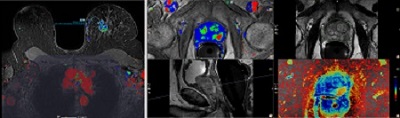

The integration of DynaCAD Breast and DynaCAD Prostate into Advanced Visualization Workspace offers dedicated workflows for diagnosis and treatment planning of breast and prostate cancers in a single advanced visualization solution with comprehensive clinical capabilities.

• Single-click volume analysis, and lesion statistics, and histograms as well as color overlay based on diffusion ADC values.

• Prostate lesions are assessed using the PIRADS v2 scoring and incorporated into standardized reports. Lesions identified and marked on the system can be passed to a UroNav system for MR/Ultrasaund fusion biopsy.